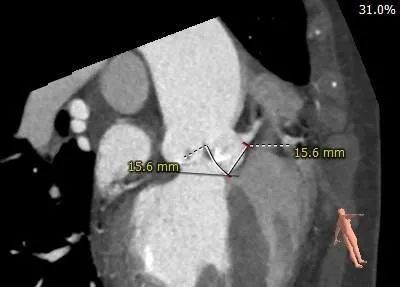

主动脉弓测量: